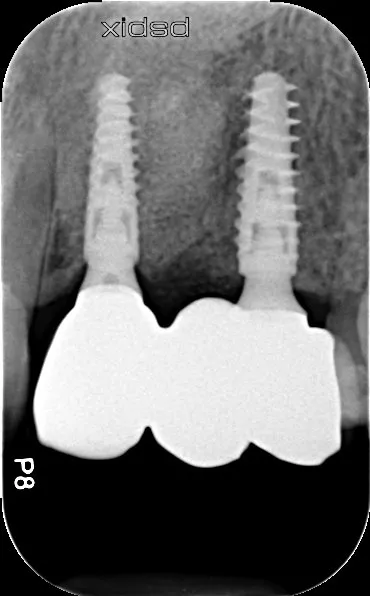

2a-b-c. Initial X-rays. The cause of the endodontic lesions was obvious, and they are underestimated on these retro-alveolar X-rays.

17a-b-c-d. Retro-alveolar X-rays at the end of treatment. Note bone behavior around the 4 implant collars. Soft tissue height above each collar was 3 to 4 mm.